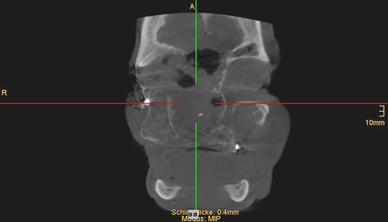

Fig. 7

Preoperative computer tomography scan showing complete destruction of the right maxilla and hard palate and bony infiltration of the orbital floor, zygomatic bone and ethmoidal cells

Bild vergrößern